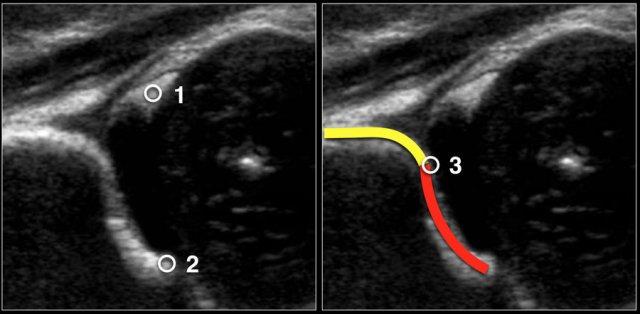

Ba điểm quan tâm đầu tiên cần được xác định trong hình ảnh:

- Centre of labrum

- Phần dưới của xương chậu (=Mặt dưới của bờ trong ổ cối nơi xương chậu gặp sụn chữ Y)

- Bờ xương của ổ cối. Khi bờ xương có góc cạnh, điểm này dễ dàng nhận biết. Khi bờ xương tròn, điểm này được xác định là nơi phần lõm của mái ổ cối xương chuyển thành phần lồi của xương chậu

Trong video này, bạn sẽ thấy cách đo lường chính xác sau khi đặt ba điểm quan tâm.

Khi thực hiện kiểm tra siêu âm, hãy đảm bảo rằng ba điểm này có thể được xác định trên hình ảnh.